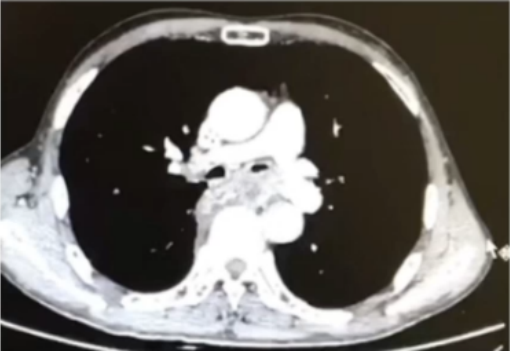

追溯患者既往病史:4月16日胸部CT显示左主支气管狭窄(图2)5月7日病理提示非小细胞癌。考虑可能是肿瘤加重导致的气道阻塞。

2  患者既往胸部CT(2021-04-16)